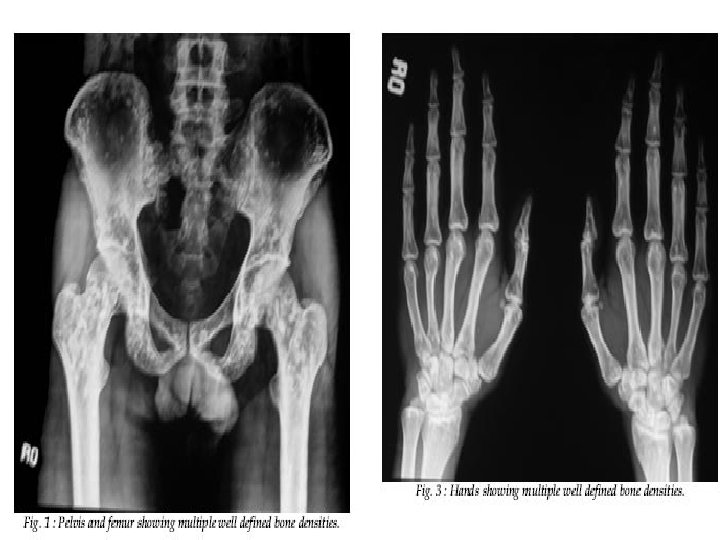

Osteopoikilosis • Uncommon benign sclerosing bone dysplasia with an autosomal dominant inheritance • It is characterized by the presence of dense spots that are round, oval, or lanceolate, with their long axes parallel to the long axis of the bone. They are usually uniformly dense, and are grouped towards the end of long bones and pelvis. • The skull, ribs, and vertebrae are usually spared. The patients may also have disseminated white spots on the skin called dermatofibrosis lenticularis disseminata.